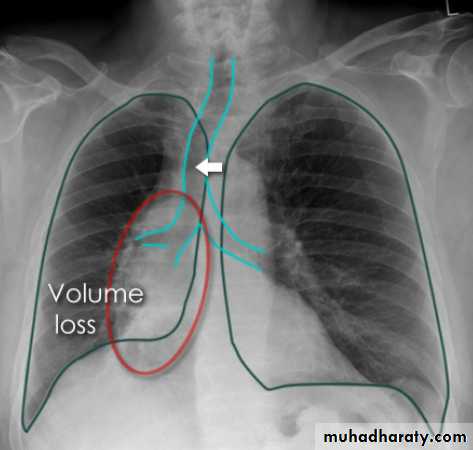

Right upper lobe collapse has distinctive features, and is usually easily identified on frontal chest radiographs .

Radiographic features

Chest radiograph

Collapse of the right upper lobe is usually relatively easy to identify on frontal radiographs. Features consist of :

increased density in the upper medial aspect of the right hemithorax

elevation of the horizontal fissure

loss of the normal right medial cardiomediastinal contour

elevation of the right hilum

hyperinflation of the right middle and lower lobe result in increased translucency of the mid and lower parts of the right lung

right juxtaphrenic peak

A common cause of lobar collapse is a hilar mass. When a right hilar mass is combined with collapse of the right upper lobe, the result is an S shape to elevated horizontal fissure. This is known as Golden S sign .

Non-specific signs indicating right sided atelectasis are also usually present including:

elevation of the hemidiaphragm

crowding of the right sided ribs

shift of the mediastinum and trachea to the right